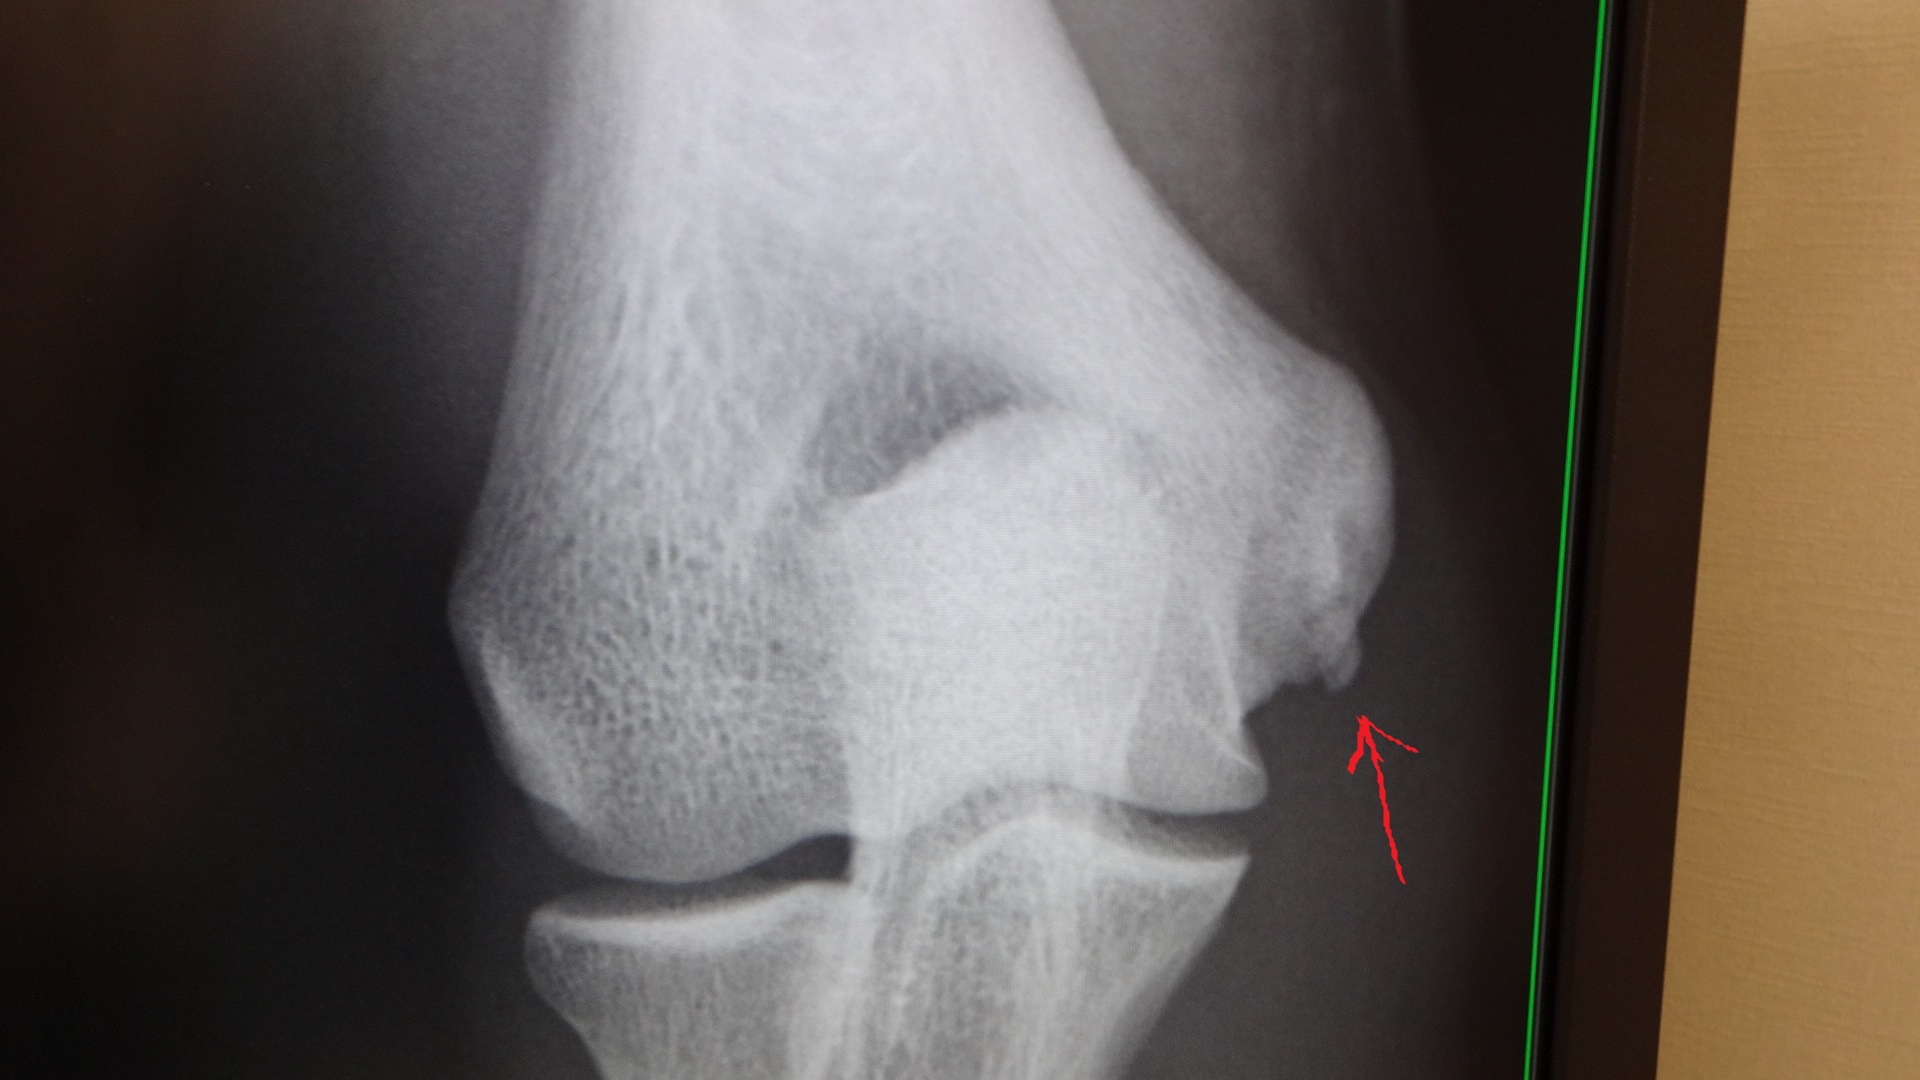

*今回のブログには、肘のレントゲン写真が載っていますので、

苦手な方は、スルーして下さい。

5月の時の肘のレントゲン写真は、

こちら。

矢印の所に、突起物が有ります。

靭帯が切れて、剥がれ掛かっているそうです。

今回の受診で、再度、レントゲンを撮ったのですが、

今回は、

この様になっていました。

突起物も、大きくなっていて、

かなり悪化しているとの事。

ピッチングは勿論の事、

バッティングも、行ってはいけないそうです。